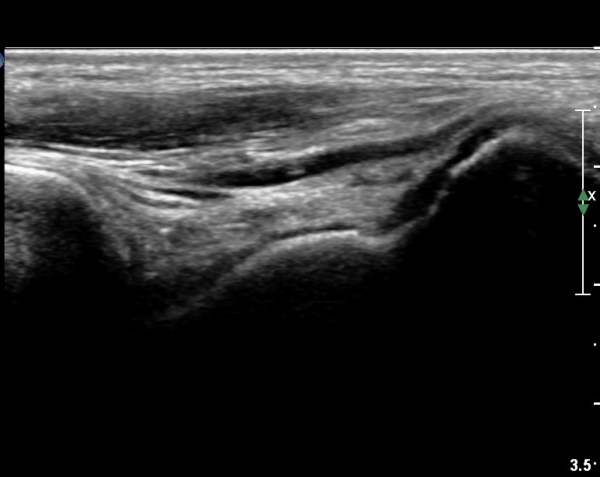

Sinus tarsi Á¾´Ü¸é, Ⱦ´Ü¸é°Ë»ç¿¡¼­ sinus tarsi ³» ºÎÁ¾À» º¸ÀÓ(»çÁø 5, 6).